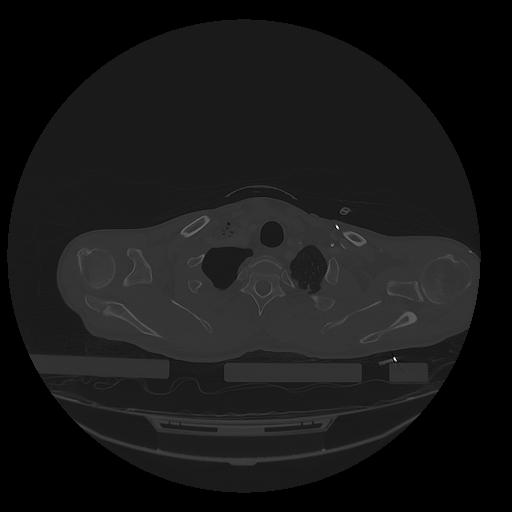

31 PULMON,CE,Vol,1.0,PULMON,,